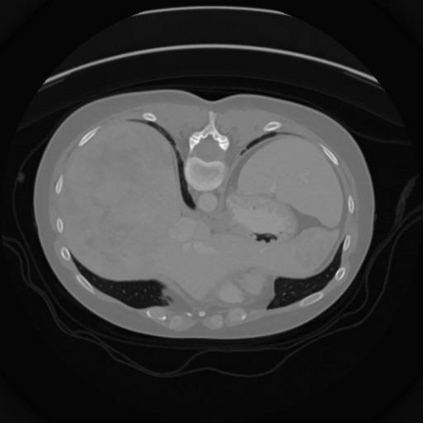

Sparse-view computed tomography (CT) -- using a small number of projections for tomographic reconstruction -- enables much lower radiation dose to patients and accelerated data acquisition. The reconstructed images, however, suffer from strong artifacts, greatly limiting their diagnostic value. Current trends for sparse-view CT turn to the raw data for better information recovery. The resultant dual-domain methods, nonetheless, suffer from secondary artifacts, especially in ultra-sparse view scenarios, and their generalization to other scanners/protocols is greatly limited. A crucial question arises: have the image post-processing methods reached the limit? Our answer is not yet. In this paper, we stick to image post-processing methods due to great flexibility and propose global representation (GloRe) distillation framework for sparse-view CT, termed GloReDi. First, we propose to learn GloRe with Fourier convolution, so each element in GloRe has an image-wide receptive field. Second, unlike methods that only use the full-view images for supervision, we propose to distill GloRe from intermediate-view reconstructed images that are readily available but not explored in previous literature. The success of GloRe distillation is attributed to two key components: representation directional distillation to align the GloRe directions, and band-pass-specific contrastive distillation to gain clinically important details. Extensive experiments demonstrate the superiority of the proposed GloReDi over the state-of-the-art methods, including dual-domain ones. The source code is available at https://github.com/longzilicart/GloReDi.